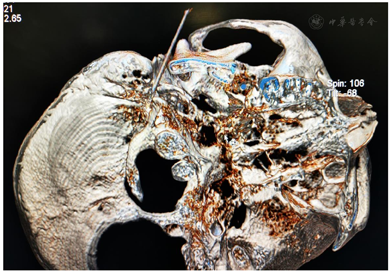

鉴于MS与HFS的临床表现有高度相似之处,我们设想,用于治疗HFS的面神经射频技术有望用治疗MS。经报请医院伦理委员会讨论通过(LS2019-013),决定给患者施行双侧面神经射频治疗。术前向患者及其家属详细交待操作经过和可能出现的轻度面神经麻痹并发症,取得知情同意并签署书面知情同意书后,嘱患者右侧向上侧卧于CT台上,安置血压、心电图、脉搏血氧饱和度监测设施并给予鼻导管吸氧,并在耳垂前后放置CT定位定位栅(图2)。用鼻旁窦模式拍摄头颅定位像,并对乳突区进行层厚3 mm轴位扫描,选取含茎乳孔且无颞骨鼓部骨质阻挡的CT层面作为穿刺层面,并在该层面上设计穿刺路径:以右侧茎乳孔为穿刺靶点,用CT自带测量工具软件由右茎乳孔向前上拉直线,该线与皮肤的交点即为穿刺点,测量穿刺深度(穿刺点至靶点的距离)和穿刺角度(穿刺路线与矢状面的夹角)(图3)。对穿刺点进行局部麻醉,用长度为10 cm、裸露端为5 mm的7号射频针在CT引导下穿刺至靶点(图4)并CT扫描三维重建观察确认(图5),随后用低频(2 Hz)电流进行运动神经刺激测试,0.5 mA电流电刺激即能诱发出右侧面肌出现与电刺激相同频率痉挛性抽动,见视频,给予65℃标准射频消融,同时嘱患者鼓腮、闭眼,射频第27秒鼓腮漏气,右眼不能紧闭,即停止射频,结束手术,见视频。2 d后同样于CT引导下行左侧茎乳孔穿刺面神经射频消融治疗(图6,图7,图8)。